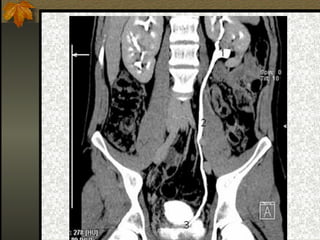

Riñones

 Dos órganos con forma de alubia.

 Situados en la parte dorsal posterior a ambos

lados de la columna.

 Se distinguen varias partes:

Cápsula: envoltura externa

Corteza renal: parte más externa.

Médula renal: parte interna.

Pelvis renal: cavidad que recoge la orina y la

conduce hasta los uréteres.

 Están formados por unidades denominadas

nefronas.

Riñones  Dos órganoscon forma de alubia.  Situados en la parte dorsal posterior a ambos lados de la columna.  Se distinguen varias partes:     Cápsula: envoltura externa Corteza renal: parte más externa. Médula renal: parte interna. Pelvis renal: cavidad que recoge la orina y la conduce hasta los uréteres.  Están formados por unidades denominadas nefronas.